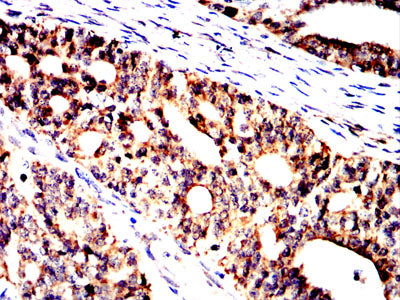

分类: 科研抗体货号: 32321别名: BST1应用: WB,IHC,FCM反应种属: Human, Mouse, Rat

分类: 科研抗体货号: 32306别名: SCDO1应用: WB,IHC,IF,FCM反应种属: Human, Rat